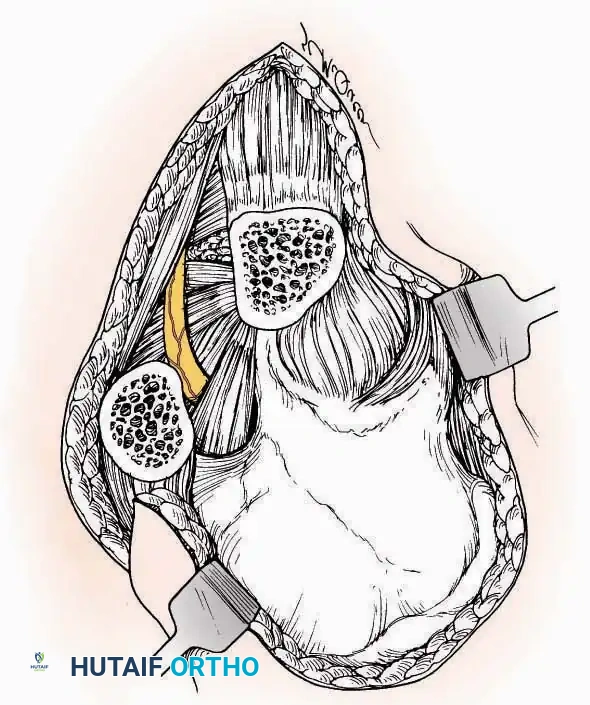

Anterolateral Approach

The anterolateral approach is widely considered the "universal incision" for the foot and ankle. It provides unparalleled access to the ankle joint, the talus, and the majority of the tarsal articulations, while safely avoiding the major anterior neurovascular bundle. The only tarsal joints inaccessible via this route are the naviculocuneiform joints (specifically the medial and intermediate).

Indications: Total talectomy, triple arthrodesis, ankle arthrodesis, and open reduction of complex talar neck fractures.

Surgical Technique:

* Incision: Begin over the anterolateral aspect of the leg, medial to the fibula and 5 cm proximal to the ankle joint line. Carry it distally over the joint, crossing the anterolateral aspect of the talar body and the calcaneocuboid joint, terminating at the base of the fourth metatarsal.

* Superficial Dissection: Incise the superficial fascia and the superior and inferior extensor retinacula down to the periosteum of the tibia and the ankle joint capsule.

* Vascular Ligation: This trajectory usually requires the identification and ligation of the anterolateral malleolar and lateral tarsal arteries.

* Nerve Protection: Retract the skin edges carefully. Identify and protect the intermediate dorsal cutaneous branches of the superficial peroneal nerve (SPN), which frequently cross the distal aspect of this incision.

* Muscle Management: Identify the origin of the extensor digitorum brevis (EDB) muscle on the lateral calcaneus. Divide it in the direction of its fibers, or detach its origin entirely and reflect it distally to expose the subtalar and calcaneocuboid joints.

* Deep Exposure: Retract the extensor digitorum longus (EDL) tendons, the dorsalis pedis artery, and the deep peroneal nerve (DPN) medially. Incise the anterior ankle capsule to expose the tibiotalar joint.

* Tarsal Exposure: Expose the talonavicular joint by dissecting deep to the extensor tendons and incising its capsule transversely. Continue laterally through the capsule of the calcaneocuboid joint. By excising the fat pad within the sinus tarsi (lateral and inferior to the talar neck), the posterior facet of the subtalar joint is brought into direct view.